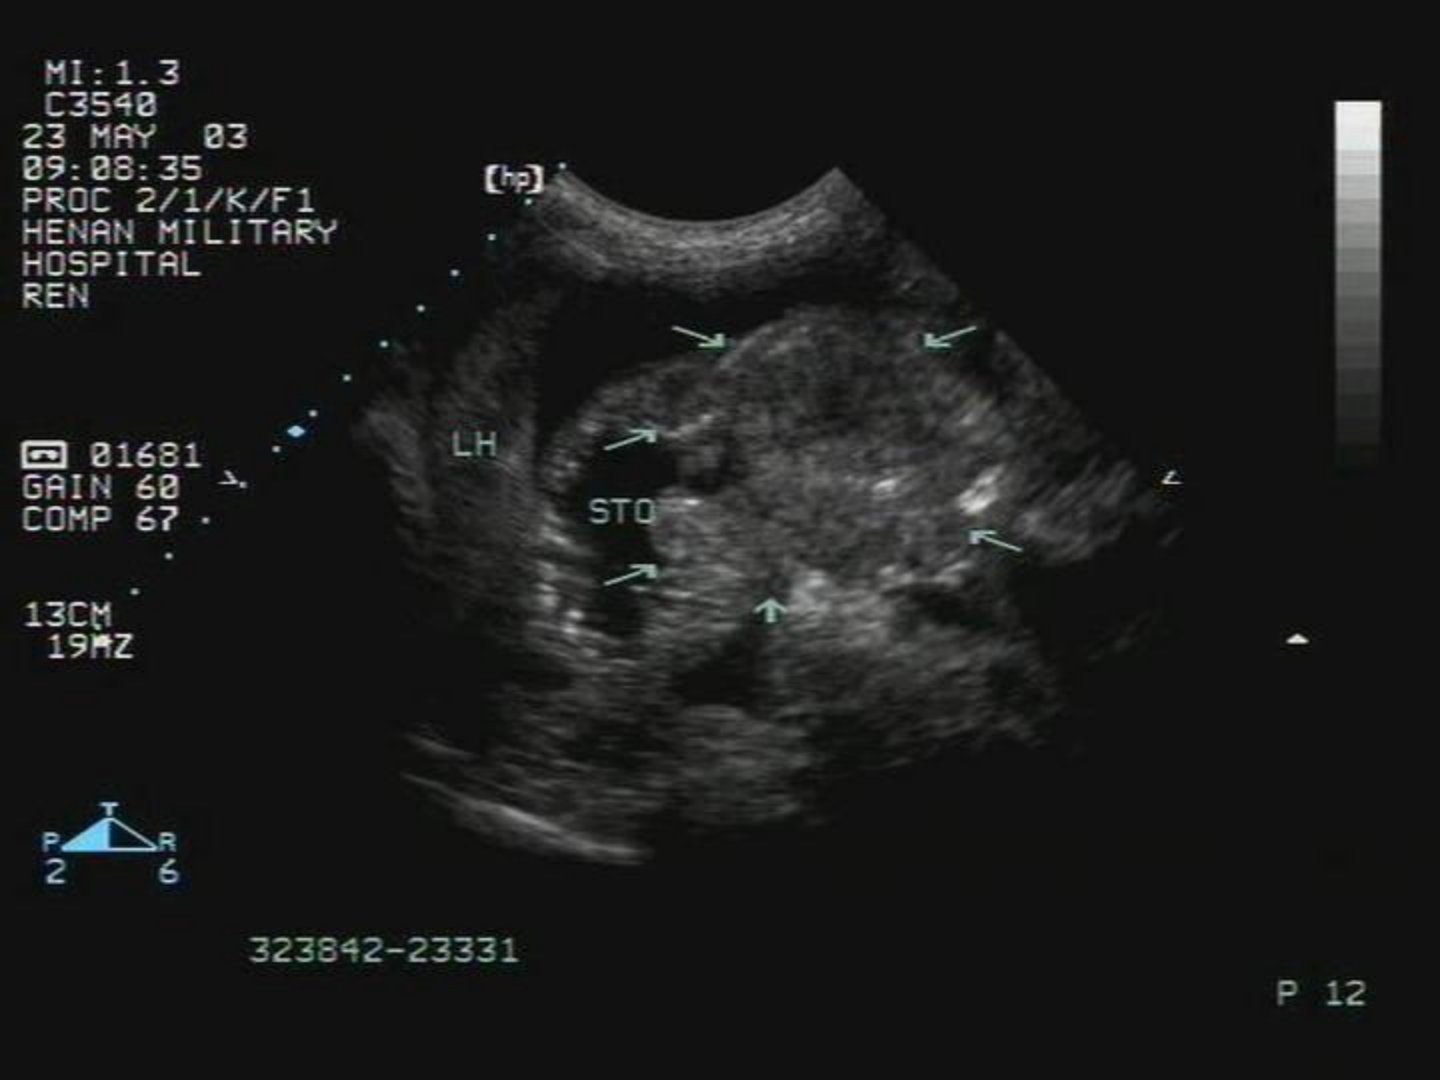

胃肠道疾病的超声诊断摘要胃肠道疾病在临床较为常见超声诊断为其提供了一种有效且无创的检查手段。超声检查可清晰显示胃肠道的形态、结构及蠕动情况。对于胃肠道炎症超声能观察到肠壁增厚、层次结构紊乱还可发现肠腔内积液等表现。在胃肠道肿瘤诊断中超声可确定肿瘤位置、大小、形态判断其浸润深度及与周围组织的关系辅助进行肿瘤分期。此外超声对胃肠道梗阻的诊断也有价值能明确梗阻部位、原因如是否因结石、肿物等导致。检查时患者通常无需特殊准备但需配合体位变动。超声诊断胃肠道疾病具有实时、动态、可重复检查等优点不过其诊断准确性也受患者体型、肠道气体干扰等因素影响必要时需结合其他检查方法以更精准地诊断胃肠道疾病为后续治疗提供可靠依据。